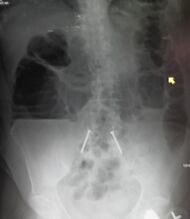

| Upright abdominal X-ray demonstrating a small bowel obstruction. Note multiple air fluid levels. | |

Radiological signs of bowel obstruction include bowel distension and the presence of multiple (more than six) gas-fluid levels on supine and erect abdominal radiographs. Ultrasounds may be as useful as CT scanning to make the diagnosis.[17]

Contrast enema or small bowel series or CT scan can be used to define the level of obstruction, whether the obstruction is partial or complete, and to help define the cause of the obstruction. The appearance of water-soluble contrast in the cecum on an abdominal radiograph within 24 hours of it being given by mouth predicts resolution of an adhesive small bowel obstruction with sensitivity of 97% and specificity of 96%.[18]